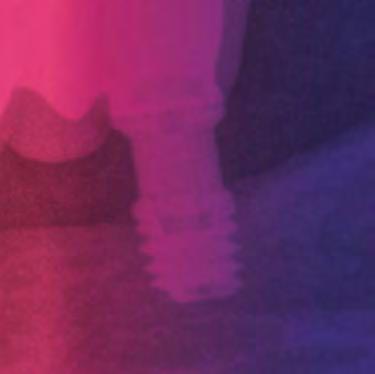

BTI Biotechnology Institute Tel: (+34) 945 140 024 | info@bticomercial.com | bti-biotechnologyinstitute.es • Carga inmediata en maxilares atróficos. • Mayor predictibilidad y menor morbilidad para el paciente. • Mayor aceptación de tratamientos. ACORTA TUS TRATAMIENTOS CON SOLUCIONES BTI www.bti-biotechnologyinstitute.com IMPLANTES CORTOS BTI DESDE SÓLO 4,5 mm. Radiografía a los 9 años